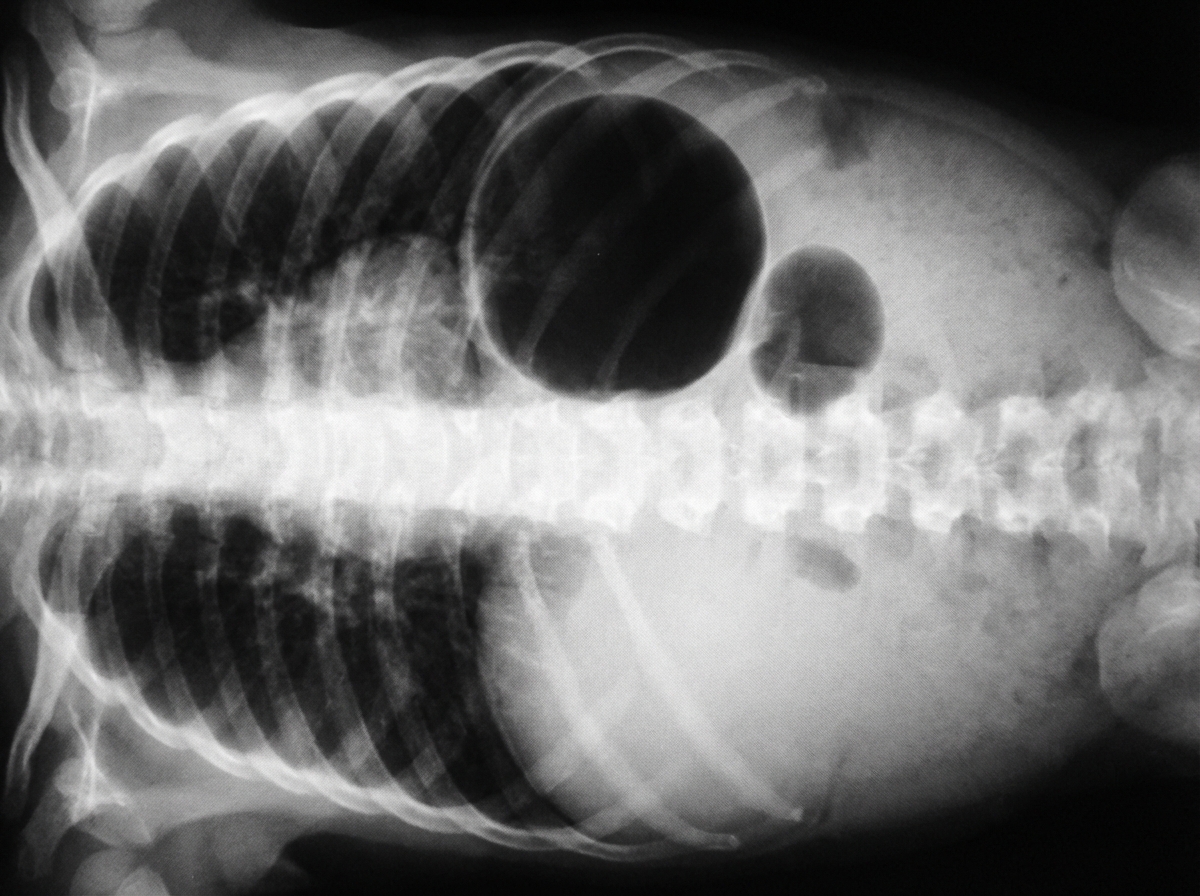

Six hours after delivery, a 3050-g (6-lb 12-oz) male newborn is noted to have feeding intolerance and several episodes of bilious vomiting. He was born at term to a healthy 35-year-old woman following a normal vaginal delivery. The pregnancy was uncomplicated, but the patient's mother had missed several of her prenatal checkups. The patient's older brother underwent surgery for pyloric stenosis as an infant. Vital signs are within normal limits. Physical examination shows epicanthus, upward slanting of the eyelids, low-set ears, and a single transverse palmar crease. The lungs are clear to auscultation. A grade 2/6 holosystolic murmur is heard at the left mid to lower sternal border. Abdominal examination shows a distended upper abdomen and a concave-shaped lower abdomen. There is no organomegaly. An x-ray of the abdomen is shown. Which of the following is the most likely diagnosis?